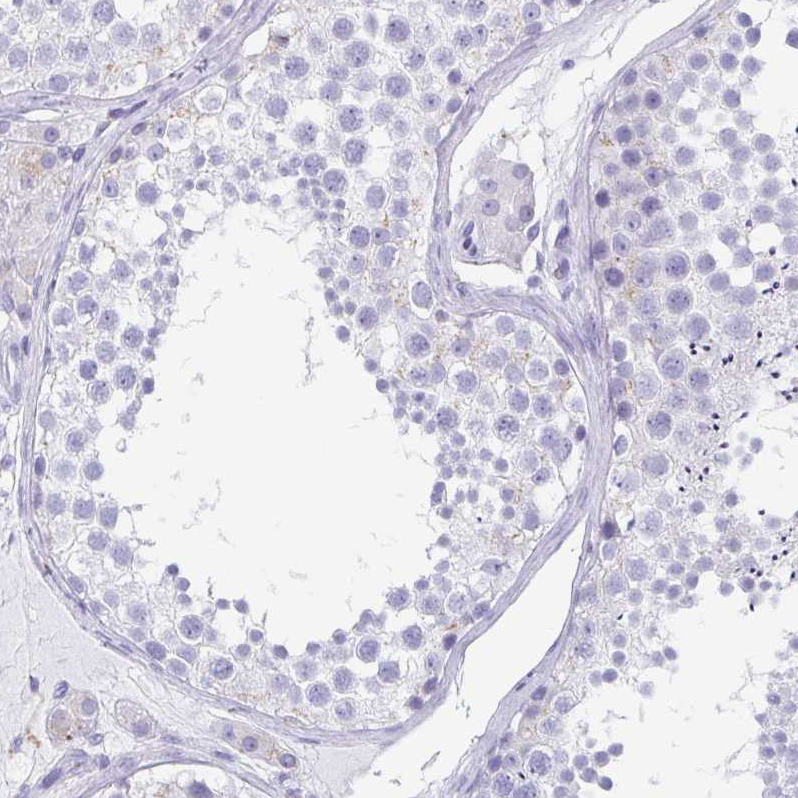

Immunohistochemistry analysis in human cerebral cortex and liver tissues using HPA062620 antibody. Corresponding TAGLN3 RNA-seq data are presented for the same tissues.